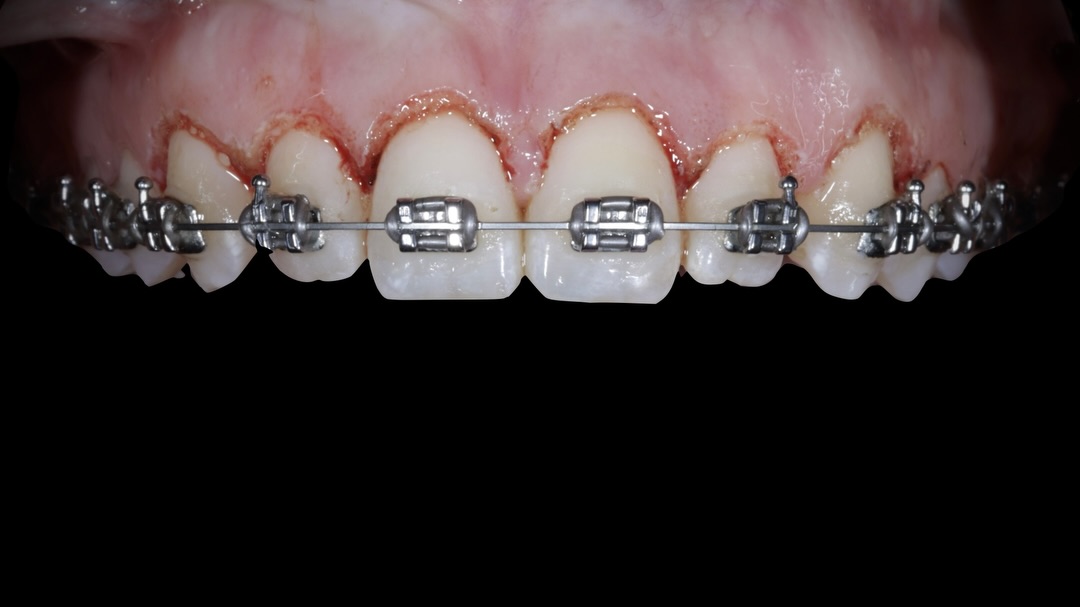

Durante esta estancia clínica tendrás la oportunidad de profundizar en las aplicaciones clínicas del láser de diodo en periodoncia, integrándolo dentro de protocolos reales de tratamiento. A lo largo de la jornada, observarás cómo se emplea el láser en procedimientos como gingivectomías, alargamientos coronarios, frenectomías y vestibuloplastias, así como su uso como coadyuvante en terapias periodontales y periimplantarias.

La formación se desarrolla en un entorno clínico real, donde el participante asiste a las intervenciones programadas y puede comprender no solo la ejecución técnica, sino también la correcta selección de casos, parámetros de configuración del láser, indicaciones, contraindicaciones y criterios clínicos que determinan su uso. Se abordarán aspectos clave como la interacción del láser con los tejidos blandos, el control del sangrado, la cicatrización y las ventajas frente a técnicas convencionales.

Esta estancia está dirigida a odontólogos de todos los niveles que deseen incorporar el láser de diodo a su práctica diaria con un enfoque seguro, predecible y basado en la evidencia clínica.